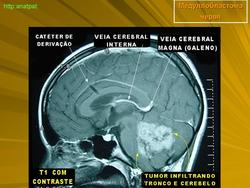

Медуллобластома - это опухоль, которая возникает из примитивных и эмбриональных клеток ЦНС. Локализируется исключительно в мозжечке и представляет 15-20% от детских опухолей мозга. 20% медуллобластом появляется в зрелом возрасте.

Это быстро растущая опухоль, очень злокачественна, имеющая тенденцию распространяться вдоль путей движения ликвора.

Вследствие локализации в мозжечке, обструкция путей циркуляции ликвора является достаточно частой и ранней, с последующей гидроцефалией. Синдром повышенного внутричерепного давления наряду с расстройствами равновесия, являются наиболее частыми и ранними признаками и симптомами.

Хирургическое лечение состоит в «радикальном» удалении опухоли, с последующей лучевой и химиотерапией, на которые медуллобластома часто очень чувствительна.

Результаты, с применением методов лучевой терапии и самыми современными схемами химиотерапии, достаточно хорошие. В настоящее время существуют больные прожившие уже более 10 лет после первой операции.